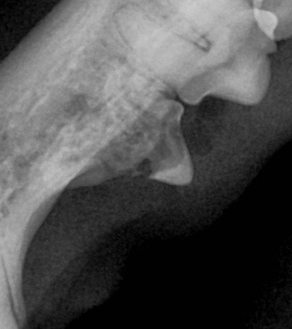

이 질환은 자연 회복이 불가능한 질환이며, 진행된 병변에 대해서는 발치가 가장 효과적인 치료법입니다.

덴탈 X-ray를 통해 치아 내부 상태를 정확히 파악한 후, 아이에게 불필요한 고통 없이 최선의 결정을 내릴 수 있도록 안내합니다.

치아흡수성병변은 치아 1개만이 아니라 여러 개가 함께 발병하는 경우도 많기 때문에, 정확한 진단과 함께 장기적인 구강 건강 계획이 중요합니다.